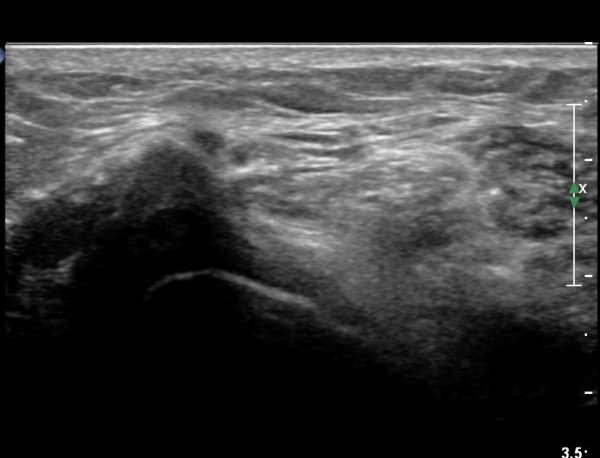

ŽÃËÀÚ¸¦ ¸»´ÜÀ¸·Î À̵¿ÇÏ´Ï À̵ιڱ٠³»Ãø¿¡¼­ ºñ°ñ½Å°æ¿Í °üÂûµÈ´Ù(»çÁø 2).